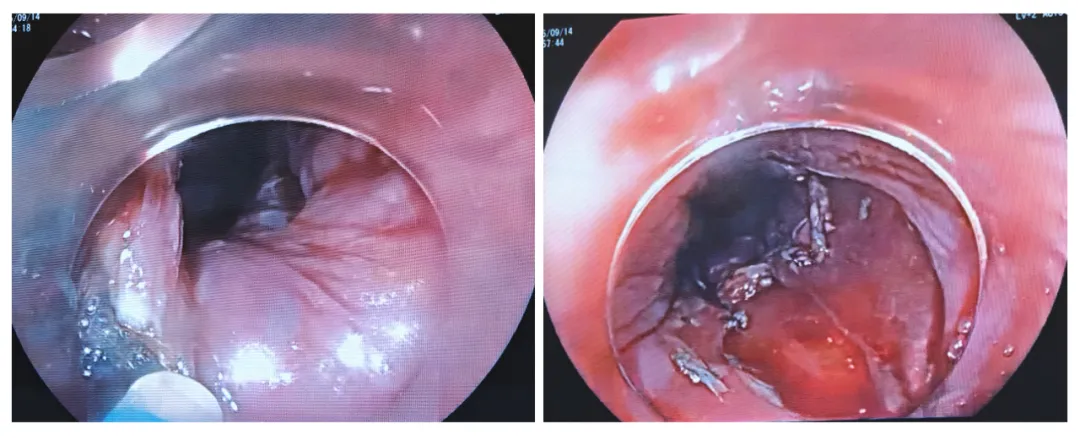

病例简介:王某,男,61岁,主诉:反复进食后腹胀5年余,加重1月。外院胃镜:食管距门齿27-32cm粘膜见粗糙,附着白色分泌物病理活检食管黏膜高级别上皮内瘤变2025年9月胃镜:食管:距门齿26cm-31cm处环腔3/4周可见黏膜粗糙,环周,不平窄带成像NBI)+放大:上皮内乳头状毛细血管网IPCL)呈B2,无血管区AVA)呈(-)碘染后不着色,边界清。胸部CT:未见明显肿物,未见肿大淋巴结。

诊断食管早癌,操作演示:内镜黏膜下剥离术(ESD),备内镜粘膜下隧道剥离术(ESTD)。演示专家中山大学附属第一医院邢象斌教授。

9:15开始,病灶在27-32cm环3/4周,操作前一天做过碘染,明确边界,对现在观察边界有点影响,不够清晰。3/4周病灶,有可能要做环周切除,术后狭窄率达80-100%会有狭窄。现在与患者家属商量是否推迟做这台ESD术。9:28与患方沟通后,家属要求继续手术,现在标记。